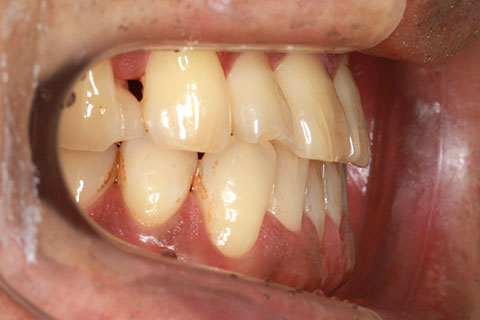

フルリンガル矯正2(上下の歯を舌側矯正で治療)

治療前

治療中

治療後

- 年齢・性別

- 42歳男性

- 治療期間

- 1年6ヶ月

- 抜歯

- なし

- 治療費

- 120万円(税込み)

- 備考

- マルチブラケットを用いた矯正治療

- 治療内容

- 反対咬合をフルリンガル矯正治療にて改善

- 施術の副作用(リスク)

- 表側矯正と比較して、歯根の角度を確立する「トルク」の力がかかりにくい。